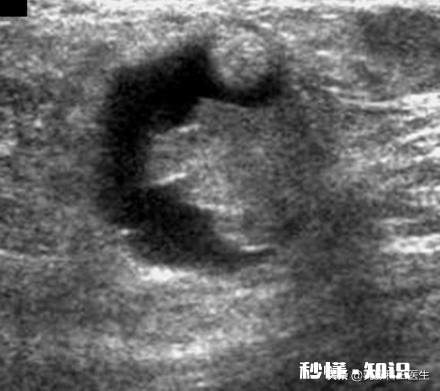

总之对于这位妈妈来说,暂时不能揉了,最好的方法先到医院做个乳房超声检查,看一下是哪种包块 。处理方法都不相同的 。有问题再留言 。母乳喂养要对自己和宝宝有信心,其实基本上不需要别人干预的,作为母乳指导通乳这个事我们也做,但是绝大部分都是指导妈妈和宝宝做,这是最自然最贴合生物本能的做法,这次疏通后还要找到涨奶的原因,针对性处理 , 避免堵奶反复发生 。

首先,你需要确定乳房上的硬块性质 。普通的堵奶原因产生的硬块不会疼痛,而且硬块边界清晰,按压下去可以明显感觉到压力感 , 能触摸到凹凸不平的乳腺体 。如果你的硬块没有压力感,按压下去会疼痛,并且会移动,那很有可能是乳房其他组织的病变 , 我建议你先去医院做一个B超,让医生帮你确定这个硬块的性质 。